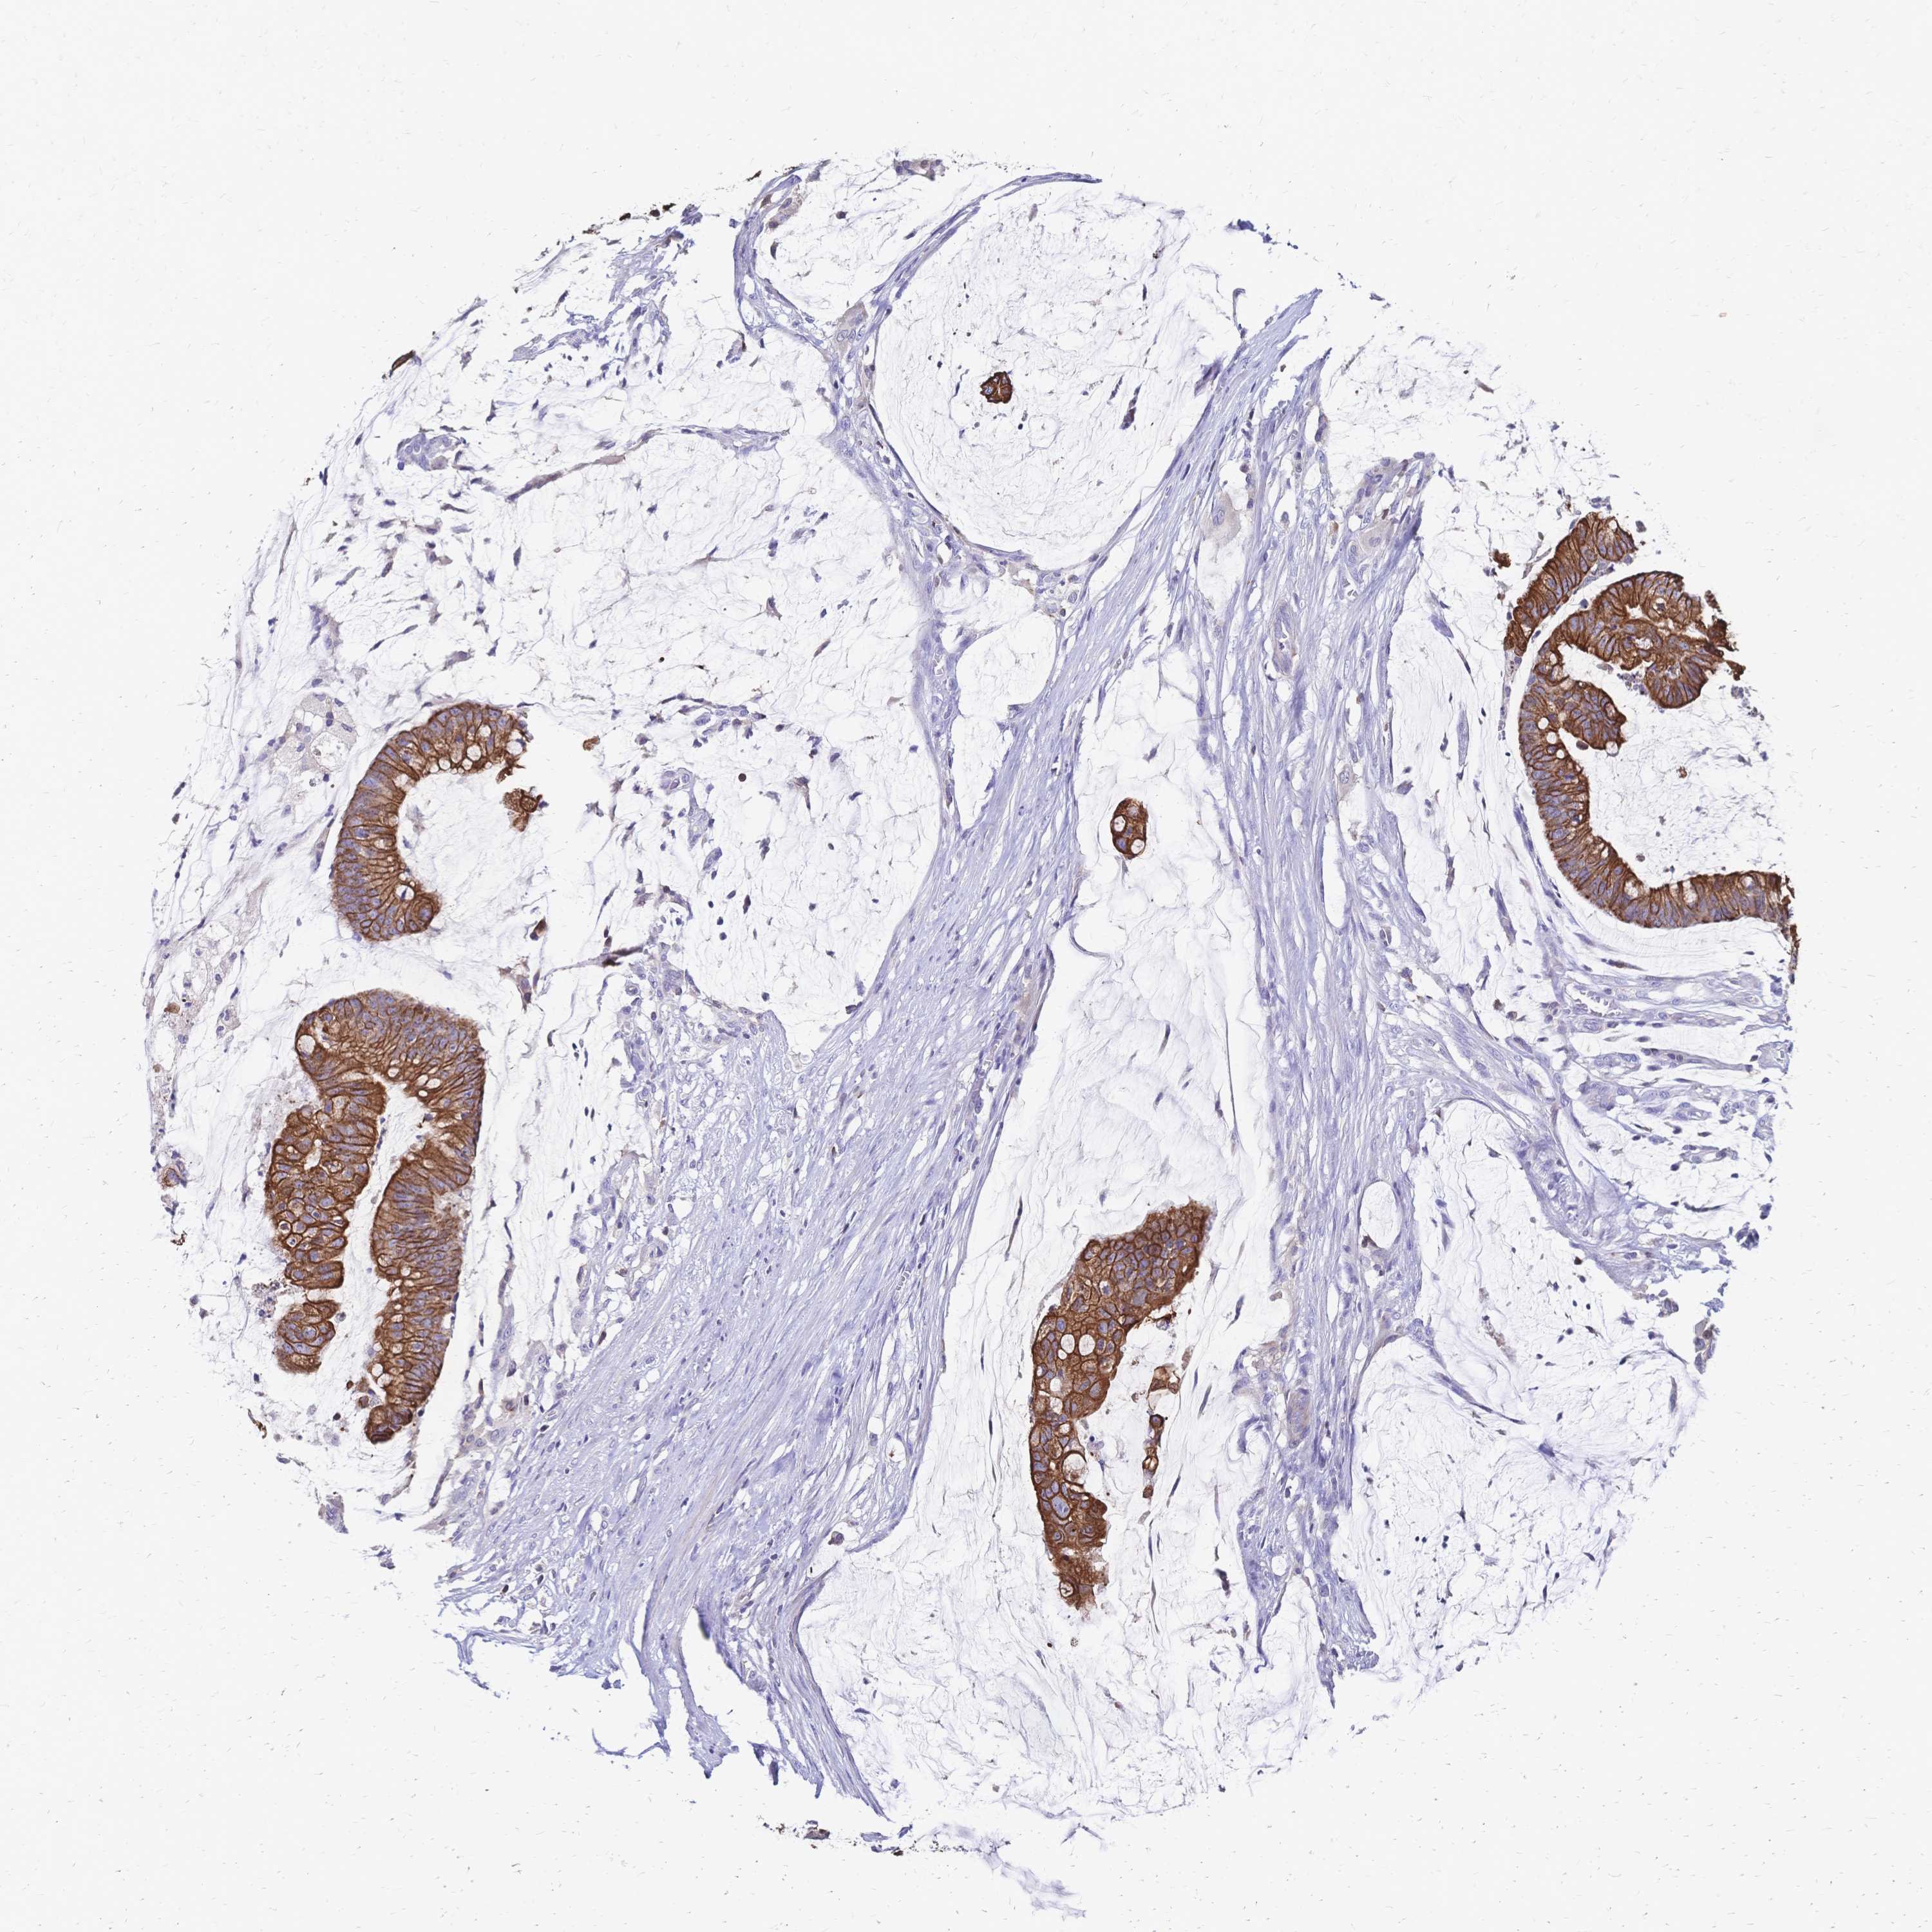

CANCER COLORECTAL CANCER Show tissue menu

COAD TCGA COAD VALIDATION READ TCGA READ VALIDATION PROTEIN COAD CPTAC PROTEIN EXPRESSION

ANTIBODIES

AND

VALIDATION